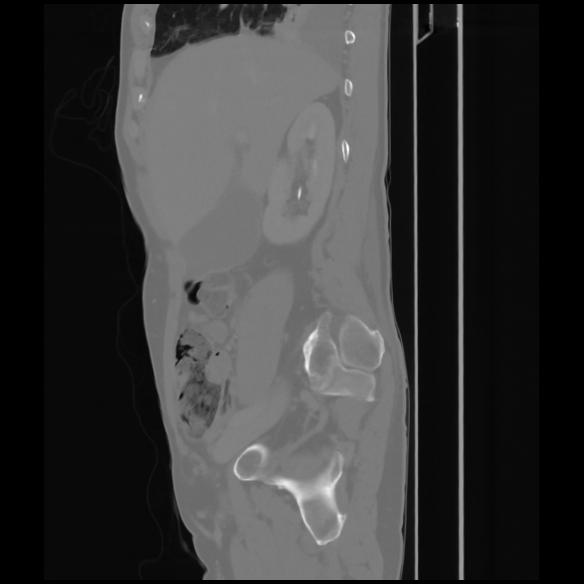

7 CUERPO,CE,Sagittal,3.000,CUERPO,Sagittal,